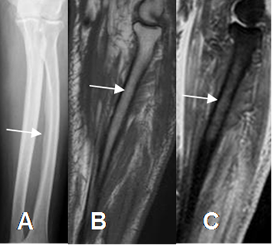

Fig 18. Edema óseo vasogénico.

A: Rx AP. Reacción perióstica en la parte medial del radio.

B: RM sagital en T1 y C: RM sagital en STIR. Alteración de la SI de la MO hipointenso en T1 e hiperintenso en STIR, por edema secundario a osteomielitis inicial.